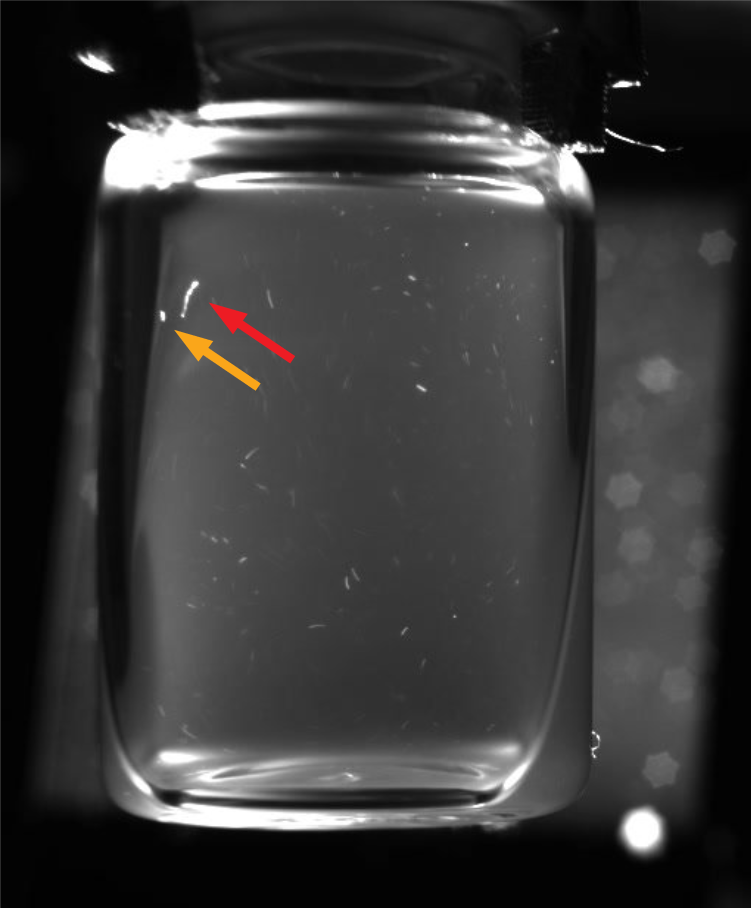

1) We outline our process for constructing a video dataset using vaccines supplied by the HAL Allergy Group. We built an automated vial rotator (AVR) for inducing the moving contrast necessary to identify anomalies [20]. However, recordings suffer from motion blur over the first 20 – 40 frames due to particles moving at a high velocity after the vial is spun (See Fig. 3). Due to motion blur good particles within the vials can appear elongated, making them hard to distinguish from anomalies. To evaluate the extent to which motion blur affects classification accuracy we split recorded samples into segments consisting of 20 frames. We hand-labelled the segments based on the presence of anomalies, enabling us to construct a dataset of 14k training and 6k evaluation samples, derived from 160 vials.

Motion Blur: One of the challenges regarding tuning the camera prior to recording the vials, was to find a depth of field that provides a sharp focus for all the particles within the suspensions. This means that the aperture size has to be narrowed to enable a sufficiently deep depth of field. A smaller aperture requires longer shutter speeds in order for sufficient light to reach the camera’s sensor. Despite increasing the light emitted by our strobe to the maximum setting, we are only able to record using 25 fps, and as a result the initial 20 – 40 frames from each recording suffer from motion blur (Examples are provided in Figure 3). Therefore, due to particles’ increased velocity after the vial is rotated using the motor, even good particles appear elongated during the initial frames of each recording.